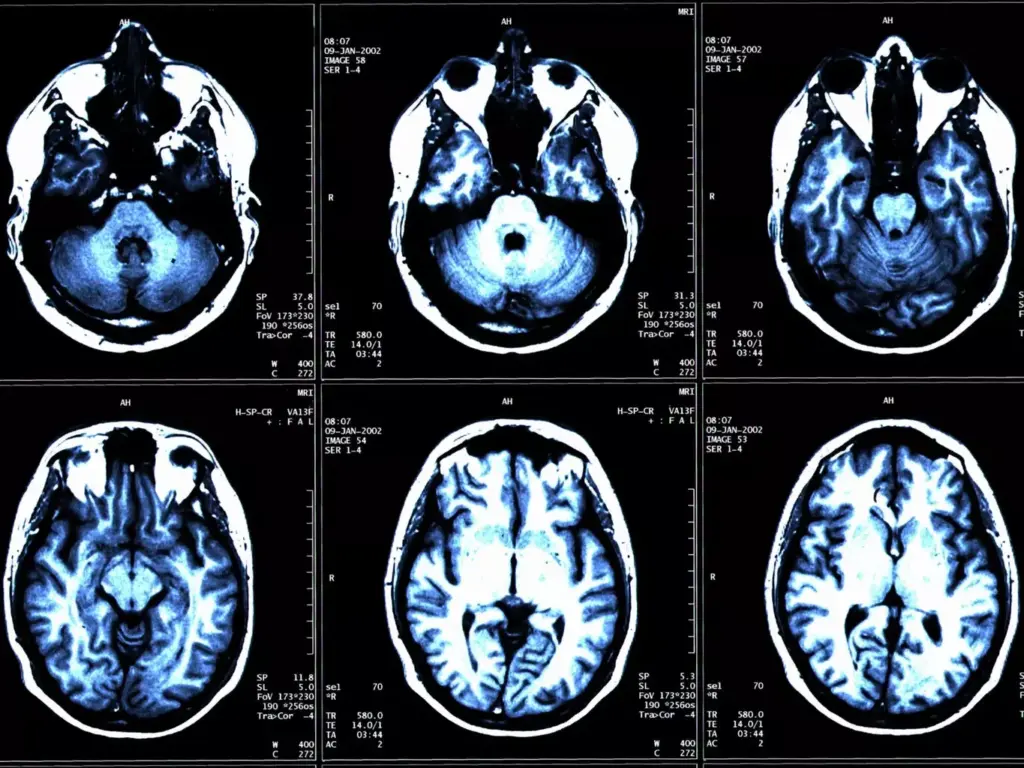

Advanced imaging is key in diagnosing and staging brain tumors. We use different imaging methods to see the tumor and its area.

Magnetic Resonance Imaging (MRI) is a top choice for brain tumors. It gives detailed brain images. This helps us see the tumor’s size, location, and details.

Computed Tomography (CT) scans are used too, mainly in emergencies or when MRI is not available. CT scans show the tumor’s structure and its effect on brain tissue.

| MRI | Detailed imaging of brain and tumor | Tumor size, location, and characteristics |

| CT Scan | Emergency or alternative imaging | Tumor structure and impact on surrounding tissue |